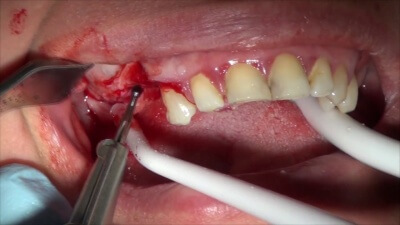

- Использование Биоимплант ГАП крошка при увеличении толщины костного гребня — читайте здесь

- Использование Биоимплант ГАП крошка при расщеплении альвеолярного отростка — читайте здесь

- Использование Биоимплант ГАП при Горизонтальной аугментации — читайте здесь